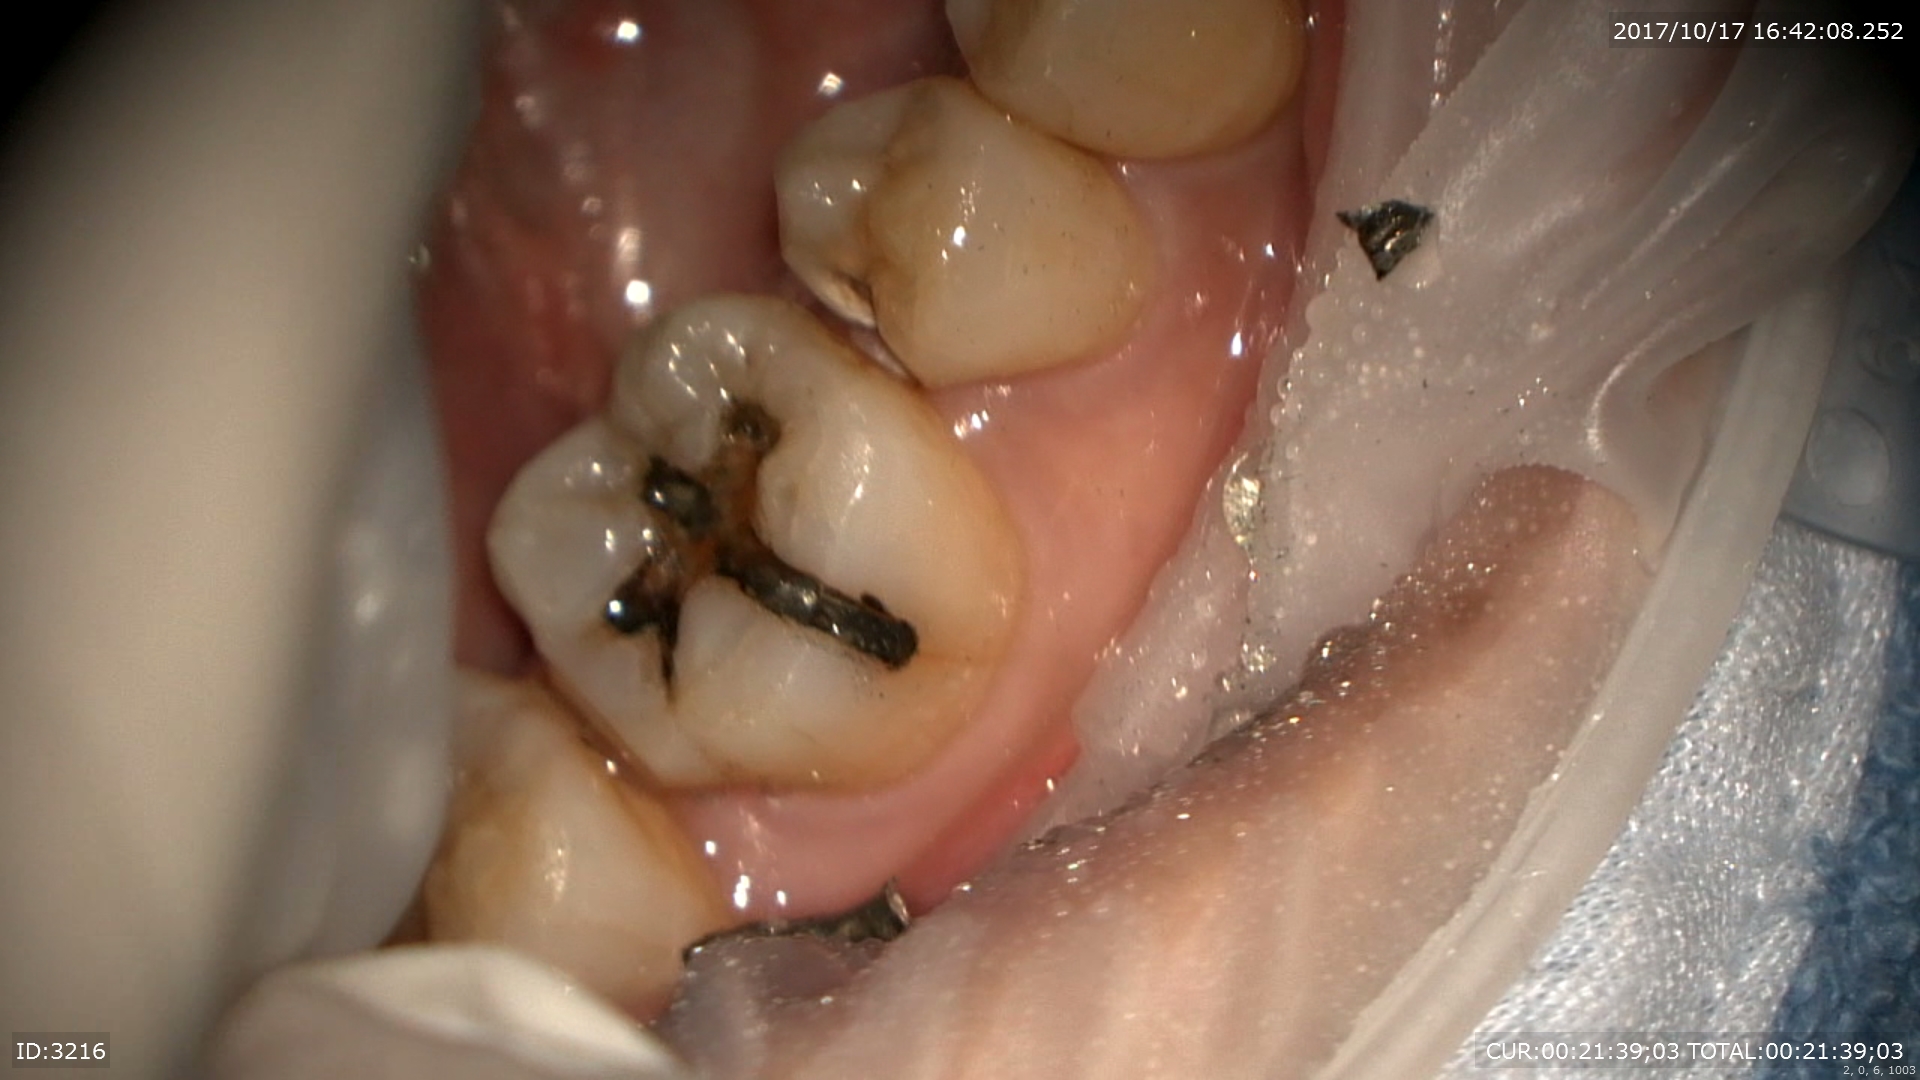

主訴:むし歯が痛い

痛そうです。

丁寧にむしばをマイクロ下で取ります。